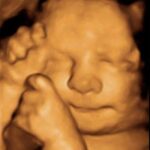

El ultrasonido 4D permite observar los rasgos y movimientos del bebé con gran claridad.

Además de lo emocional, tiene un rol clínico importante: ayuda a evaluar el bienestar fetal, detectar malformaciones y monitorear el desarrollo del embarazo.

Ecodiagnóstica cuenta con especialistas en imagen obstétrica para brindar estudios seguros y confiables.